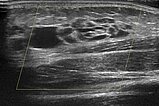

Zum gleichen Zeitpunkt, farbkodierte Duplexsonographie der Läsion. Es handelt sich klar um eine Slow-flow-Läsion mit niedrigem Durchfluss, keine Farbsignale innerhalb der Läsion. Aufgebaut ist sie aus echoarmen, zystisch erscheinenden Räumen mit dünner Wandung und echofreiem Inhalt.